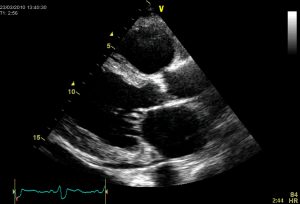

其次,心脏瓣膜病的评估和管理正在变得越来越复杂,然而许多心脏瓣膜病的患者仍被一般的医生或心脏病学家都在没有专业专业知识。对于可能缺乏诊断的医生或心脏病学家对这种疾病的评估可能难以做出诊断的诊断,特别是在确定患者是否真正无症状。该决定用于共存二尖瓣反流(一种无能或漏水的二尖瓣,使得通过心脏的血液向后流动)或者在冠状动脉旁路接枝时更换具有温和或中等狭窄的主动脉瓣的可取性也是如此经常难。瓣膜病评估涉及多种方式的整合,并且实践的进步可能比具有专业专业知识的心脏病专业的通用主义者更慢入。心脏瓣膜疾病的患者通常具有可造成症状的合并症,从而将决策复杂化,如果指出干预。确定正确的程序,无论是修复,替代或经沟管手术,都不简单,还需要专业知识,经验和多学科讨论。